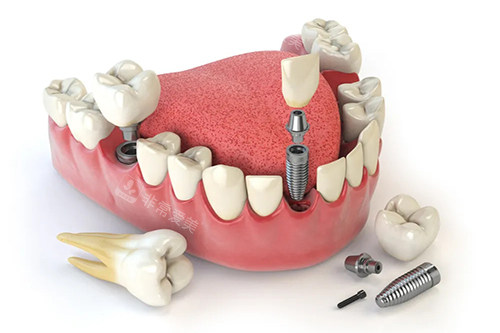

牙齿种植卡通示意图

二、进口植体品牌全体现在哪里?

汉中小虎牙口腔拥有丰富多样的进口植体品牌。

在这里,患者可以根据自身的经济状况、口腔条件等因素,自由选择适合自己的植体。

无论是来自欧美地区有名高、质量出色的植体品牌,还是日韩性价比高的植体品牌,医院都有涵盖。

齐全的植体品牌可供患者多方位选择,确保每一位患者都能找到比较为匹配自身需求的牙齿种植解决方案,让患者不再因选择有限而发愁。